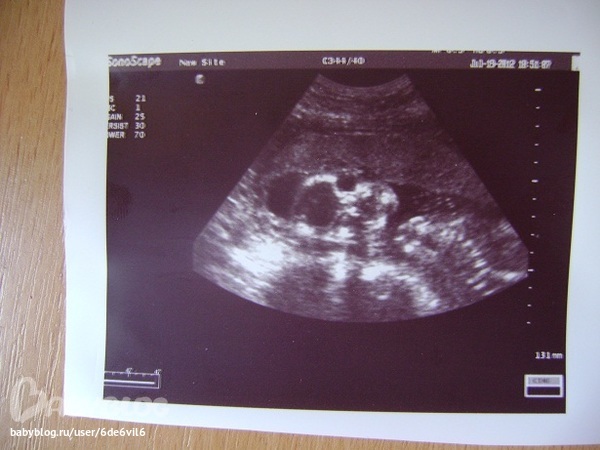

это ляля повернулась к нам лицом и смотрит на нас,это голова,темное-мозг,потом глазницы темные,носовая косточка и губки,на боку лежит)))понятно?